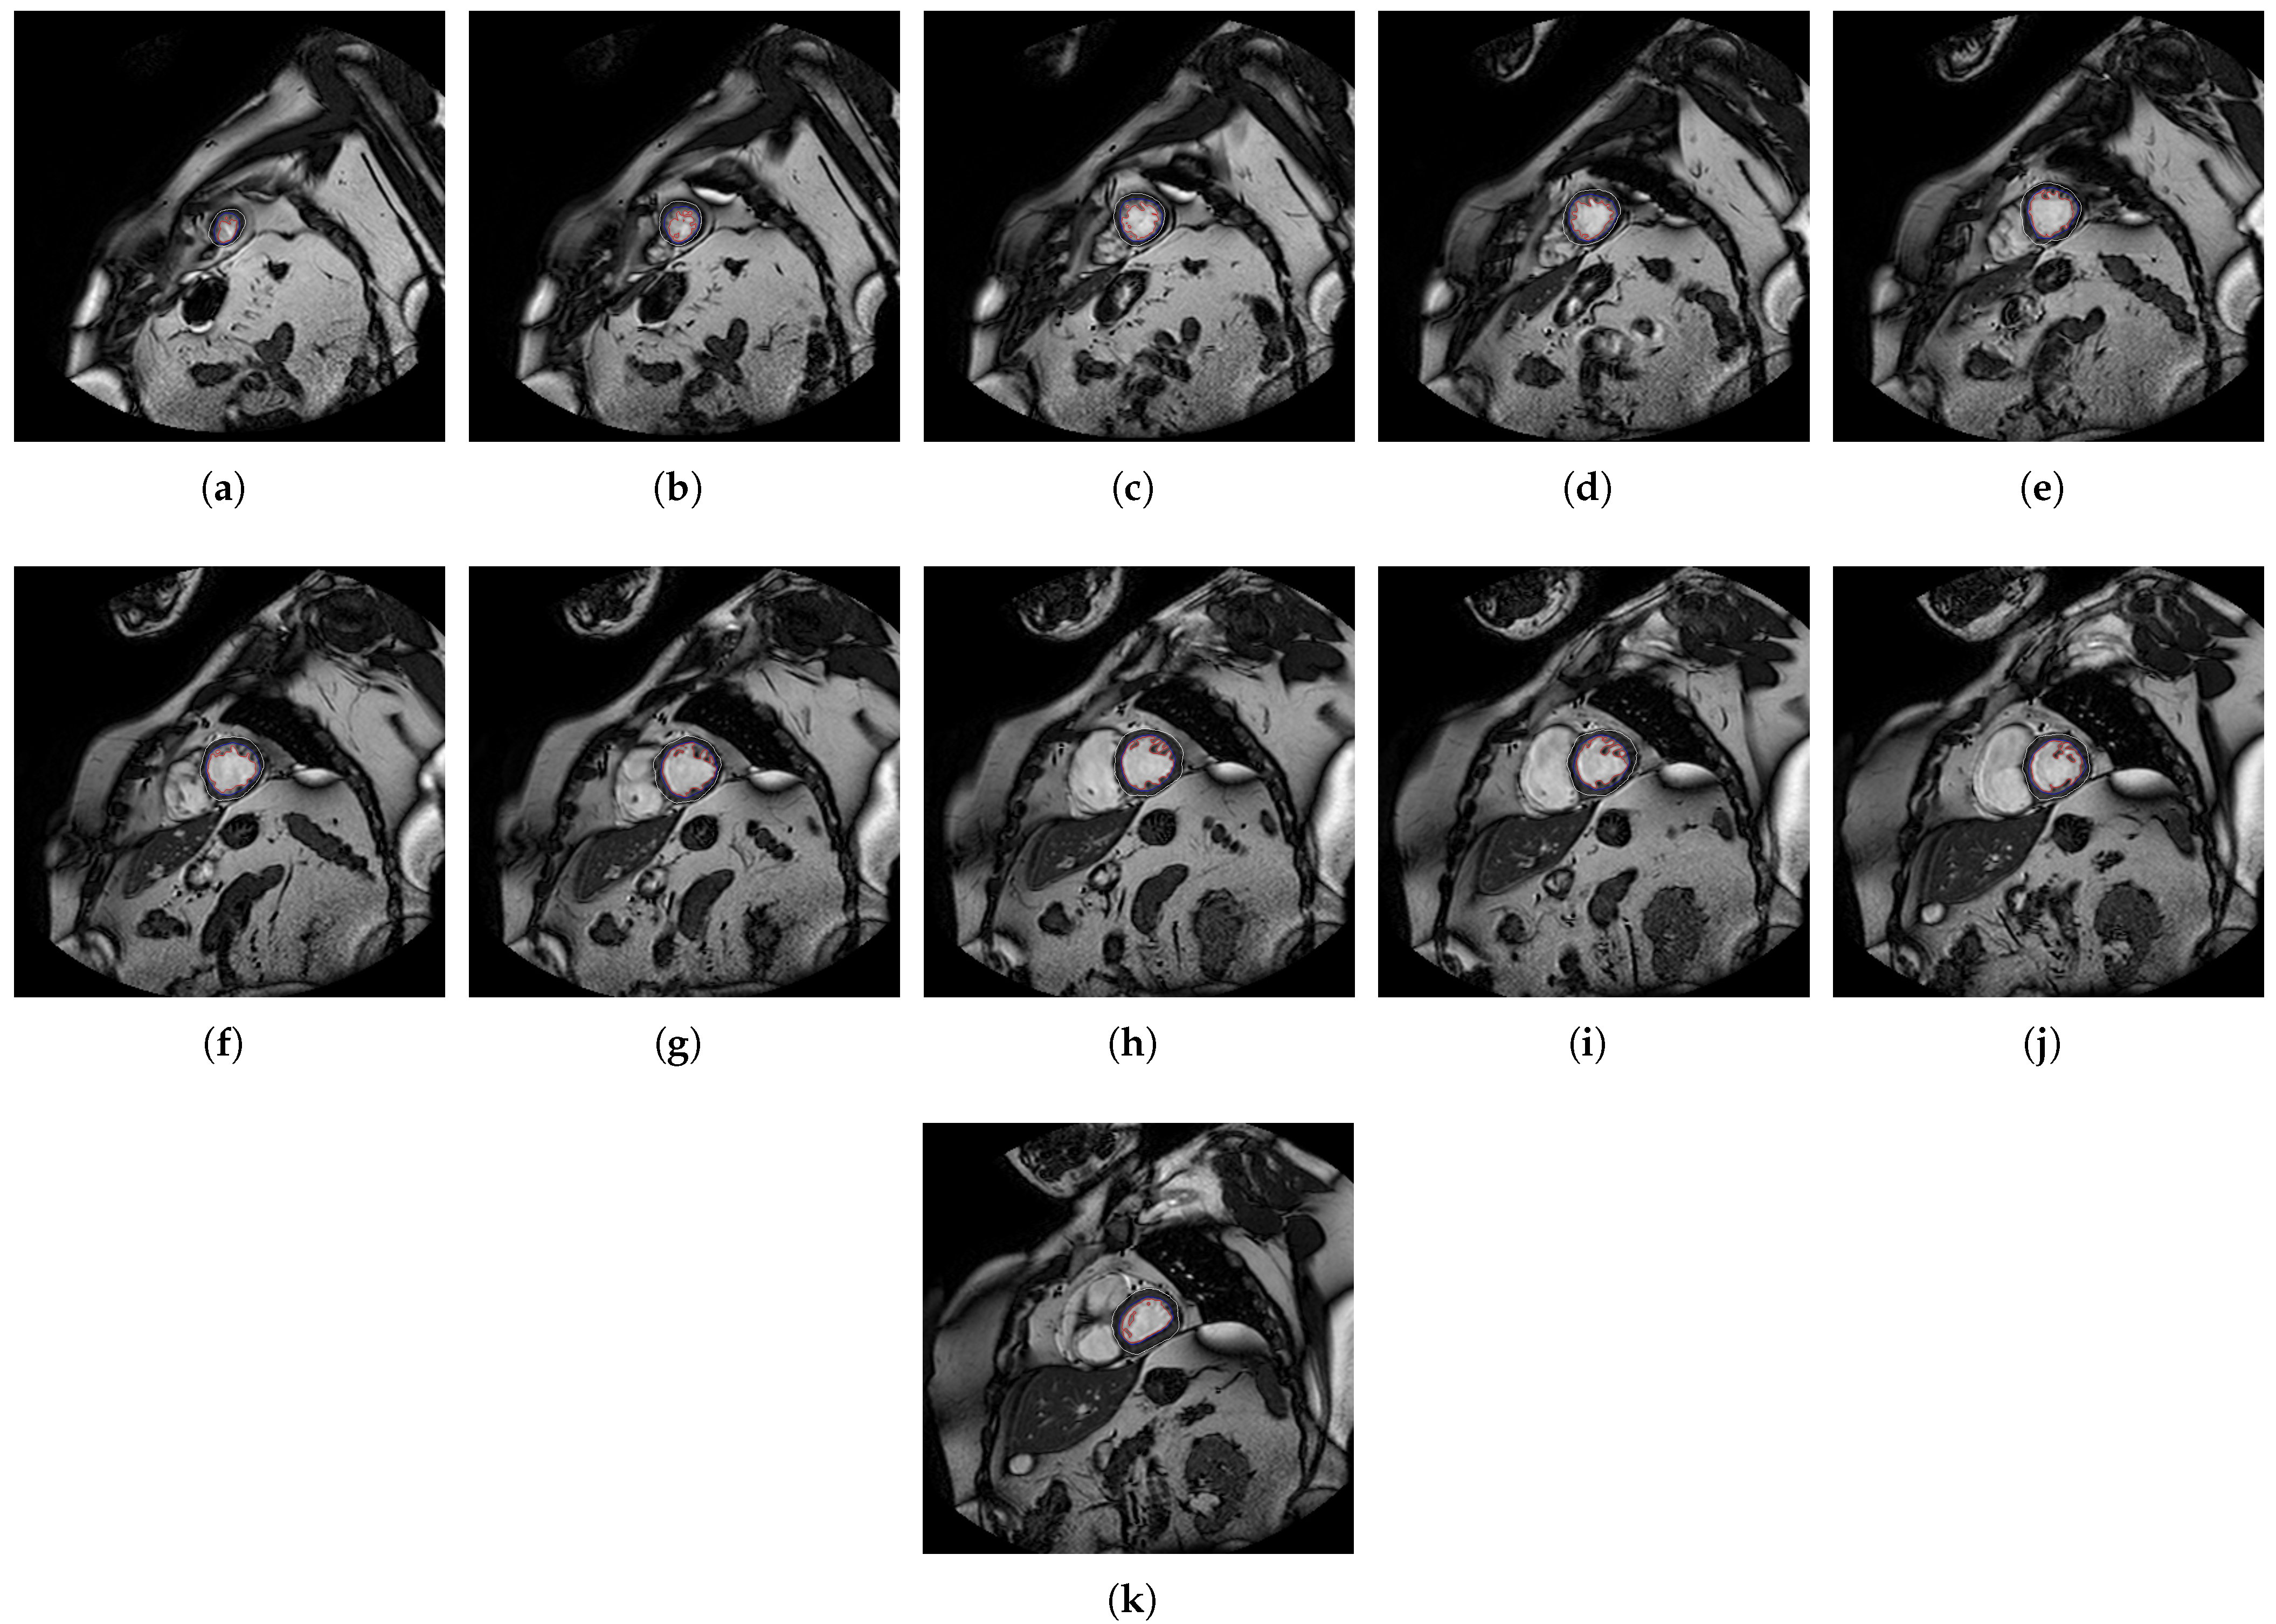

2. Methods

2.1. A Software Tool to Quantify the Trabeculae Degree in the LV Myocardium for a Population of Patients with Genetic Cardiomyopathies (QLVTHCI)

- The different MSERs are detected in a centered ROI of each input image by the use of OpenCV [23]. As the LV cavity is normally represented by a circular shape, the centroid of each MSER detected is computed in order to automatically identify the left ventricle cavity anywhere in the image and for applying the convex hull.

- The previous application of the convex hull allows a second refining to optimize the search process of the external layer and the trabeculae areas. The parameter e-expand is redefined and adjusted to accurately determine the external layer of the compact zone, thanks to plotting several lines from the centroid of the LV to reach the points of the external layer. This parameter establishes the distance of the lines between the centroid of the LV cavity and the possible space where the external layer can be found, taking into account the particular features of genetic cardiomyopathies. We optimized the parameter e-expand for different situations or possible cardiomyopathies.

- The accurate and reliable detection of the RV cavity at any location of a slice.

- The automatic processing of the slices stored in reverse order (from basal to apical).

| Patient | B1 | B2 | B3 | M1 | M2 | M3 | A1 | A2 | A3 |

| P4-FD | 1.08 | 1.17 | 1.32 | 1.27 | 1.21 | 1.31 | 1.11 | ||

| P4-TM% | 19.15 | 31.14 | 36.11 | 30.39 | 40.69 | 29.88 | 29.96 | ||

| P7-FD | 1.10 | 1.14 | 1.20 | 1.20 | 1.13 | 1.19 | 1.31 | 1.27 | 1.44 |

| P7-TM% | 28.61 | 21.14 | 39.59 | 44.45 | 44.60 | 38.53 | 32.41 | 48.67 | 34.36 |

| P13-FD | 1.13 | 1.21 | 1.35 | 1.27 | 1.28 | 1.31 | 1.24 | 1.06 | 1.11 |

| p13-TM% | 0.81 | 24.77 | 33.29 | 44.75 | 46.19 | 49.17 | 51.89 | 43.59 | 30.38 |

| P15-FD | 1.22 | 1.26 | 1.23 | 1.18 | 1.18 | 1.21 | 1.17 | 1.27 | |

| P15-TM% | 48.14 | 43.79 | 37.44 | 35.61 | 25.12 | 31.16 | 45.73 | 30.33 | |

| P20-FD | 1.17 | 1.23 | 1.20 | 1.33 | 1.33 | 1.21 | 1.20 | 1.22 | |

| P20-TM% | 35.44 | 36.20 | 31.02 | 41.35 | 34.06 | 25.64 | 18.21 | 18.87 | |

| P27-FD | 1.19 | 1.17 | 1.17 | 1.18 | 1.25 | 1.14 | |||

| P27-TM% | 33.83 | 36.73 | 34.61 | 26.01 | 22.46 | 35.93 | |||